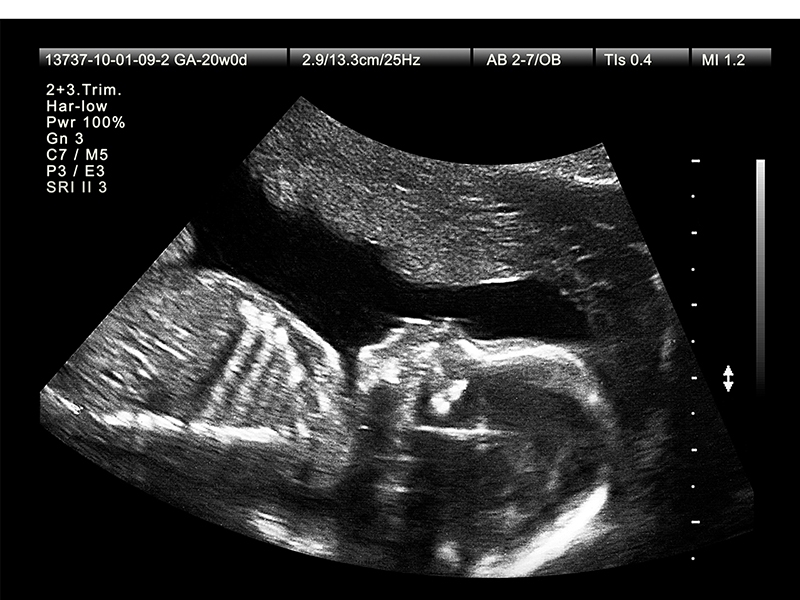

Đình chỉ hành nghề khám bệnh, chữa bệnh đối với người có hành vi thông báo, tiết lộ giới tính thai nhi để phá thai. Việc đình chỉ hành nghề khám bệnh, chữa bệnh thực hiện theo quy định của pháp luật về khám bệnh, chữa bệnh.

Cụ thể, thay vì khuyến khích mỗi cặp đôi chỉ có từ 1 đến 2 con như quy định cũ, luật mới trao quyền tự quyết về thời gian sinh con, số con và khoảng cách giữa các lần sinh phù hợp với lứa tuổi, tình trạng sức khỏe, điều kiện học tập, lao động, thu nhập và nuôi dạy con của mỗi cá nhân, cặp vợ chồng trên cơ sở bình đẳng.